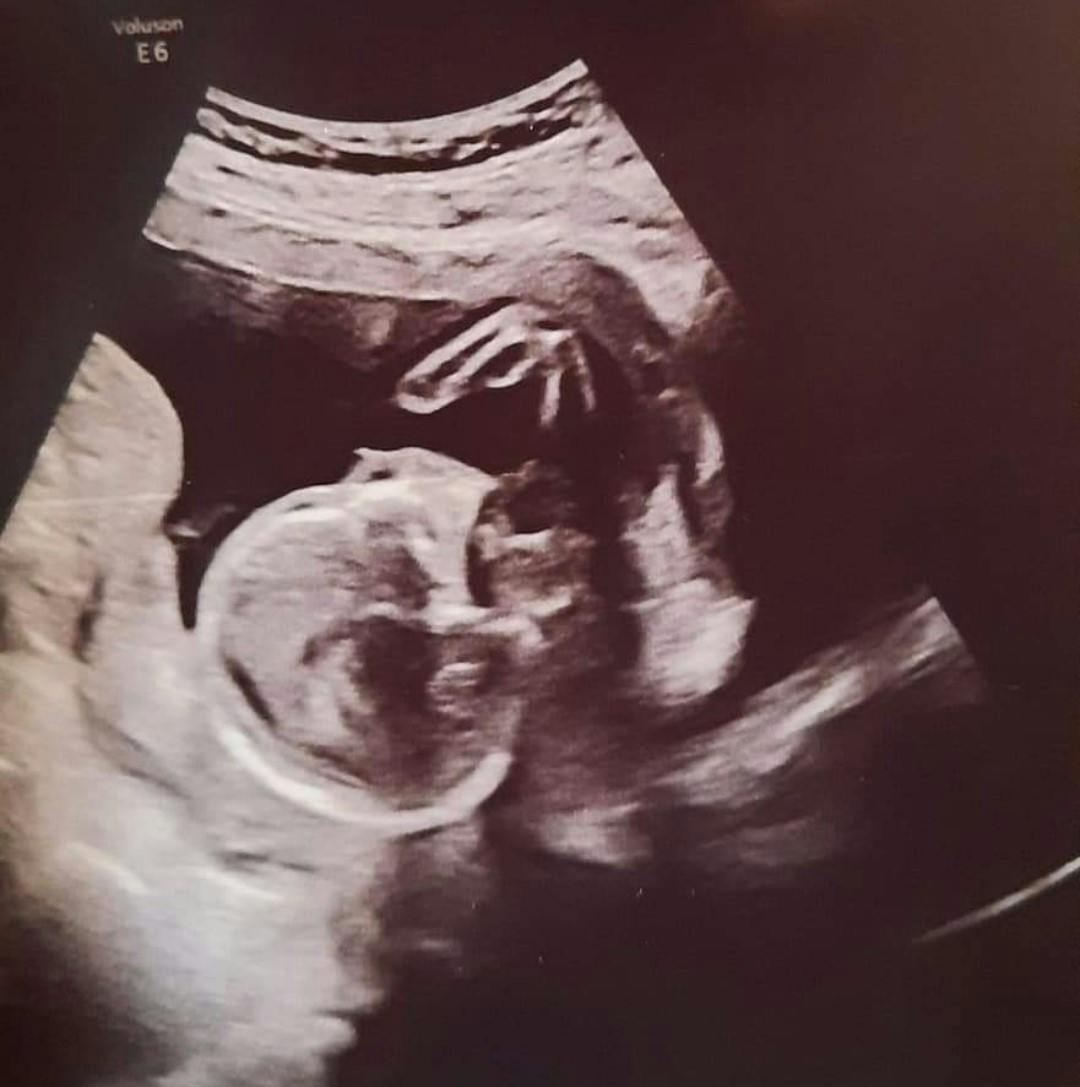

En ultralydsscanning i ottende uge bekræftede graviditeten. Alt så fint ud. Gentesten i 10. uge viste intet unormalt. Scanninger i 12. og 15. uge viste, at alt var godt.

Men da Heather blev scannet i 18. uge, var det svært at få et ordentligt billede af fostret og alle hans lemmer og organer. Han lå krummet sammen og bevægede kun armene en smule. Han sparkede ikke.

Da Heather, Jason og Jack kom tilbage til en ny scanning en uge senere, væltede verden.

Men hun fik lært en del anatomi og kunne godt selv se på scanningsbillederne, at der var noget galt med hendes babys ryghvirvler. Og at hjertet opførte sig som en våd svamp, der blev vredet.